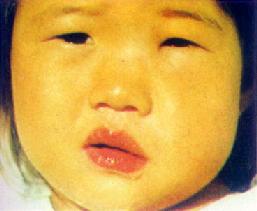

局部表现为颌下区红肿、疼痛,皮纹消失、皮肤发亮,下颌下缘可因肿胀而不显(附图14)。严重的颌下蜂窝织炎可蔓延至邻近间隙或颈部。

| 附图13 眶下蜂窝织炎(左) | 附图14眶下蜂窝织炎(右) |